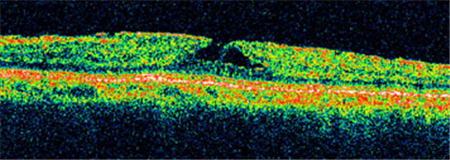

?、衿邳S斑裂孔通常無需手術,若裂孔惡化至Ⅱ-Ⅳ期就需要考慮進行手術治療。上海眼科醫院排名通過學相干斷層掃描來診斷黃斑裂孔,可清楚照出玻璃體及視網膜的情況,了解患者黃斑裂孔的大小、位置等。